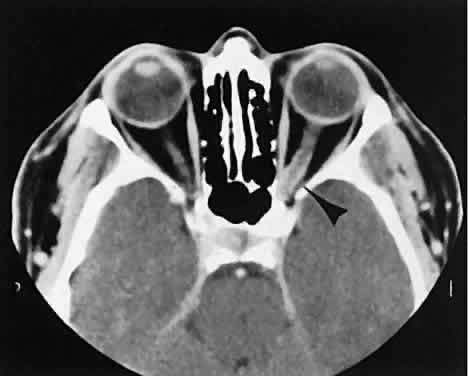

The orbital manifestations of a vascular process are dependent on whether the lesion is on the venous or the arterial circulation. Patients with venous lesions (varix) characteristically report a history of intermittent proptosis with either a Valsalva's-type maneuver or having the head in a dependent position. Suspicion of a venous varix should alert the radiologist to perform the scan before and after a Valsalva's maneuver.9,10 Color flow doppler imaging showing reversal of flow during a Valsalva maneuver also is a helpful finding. Phleboliths may or may not be present. Another clue to the diagnosis of a varix is the location, many times in the posterior, inferior lateral orbit, seemingly coming out of the inferior orbital fissure near the apex. Lesions that appear to change size or shape from the axial view to the coronal view also have turned out to represent a varix based on our experience (Fig. 2).

Fig. 2. Orbital varix. A. Axial view shows a small soft tissue mass within the inferolateral left orbital apex. B. Coronal view with patient repositioned prone with neck extension. Increased venous pressure distends the varix, accounting for increased size.